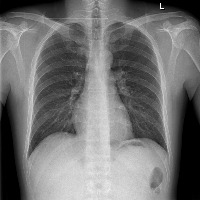

clinical_finding Computer Vision Project

Classes (38)

airspace opacity

atelectasis

bone lesion

bronchiectasis

bullae

calcified nodule

consolidation

costophrenic angle blunting

cyst-bullae

elevated hemidiaphragm

emphysema

enlarged cardiac silhouette

enlarged hilum

foreign matter

hernia

hydropneumothorax

hyperaeration

increased reticular markings

interstitial lung disease

lung opacity

mediastinal displacement

mediastinal widening

nodule

parenchymal scarring

peural thickening

pleural effusion

pneumothorax

pulmonary edema

rib fracture

scoliosis

shoulder osteoarthritis

spinal degenerative changes

subcutaneous air

superior mediastinal mass-enlargement

tortuous aorta

vascular calcification

vascular congestion

vascular redistribution